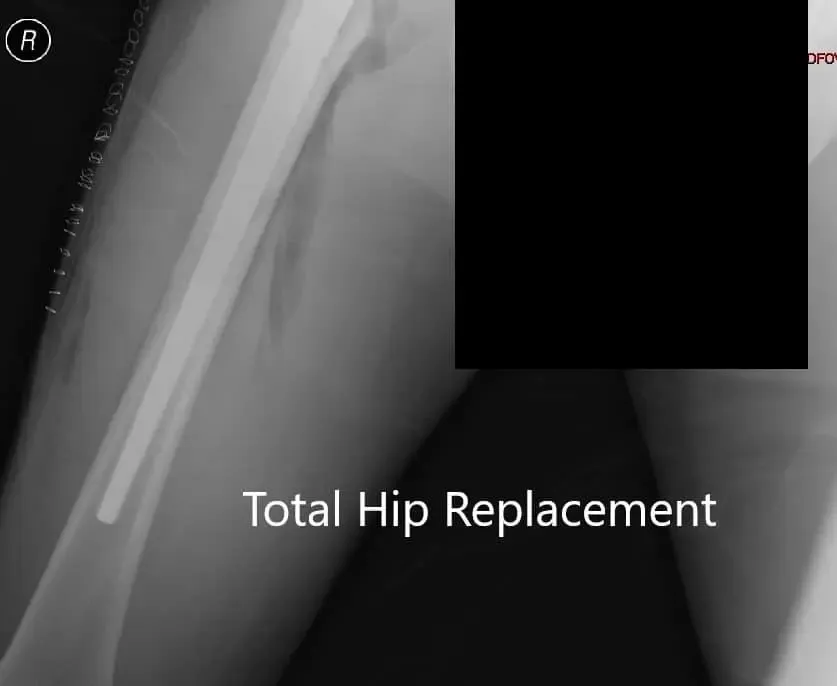

Postoperative X-ray showing AP view of the pelvis.

The recovery of the patient was unremarkable. He was started on aspirin 325mg BID for deep vein thrombosis prophylaxis. The pain was managed with medications. Hip precautions were explained to the patient. Weight-bearing was allowed as tolerated. Postoperatively there was no neurological deficit in bilateral lower extremities.